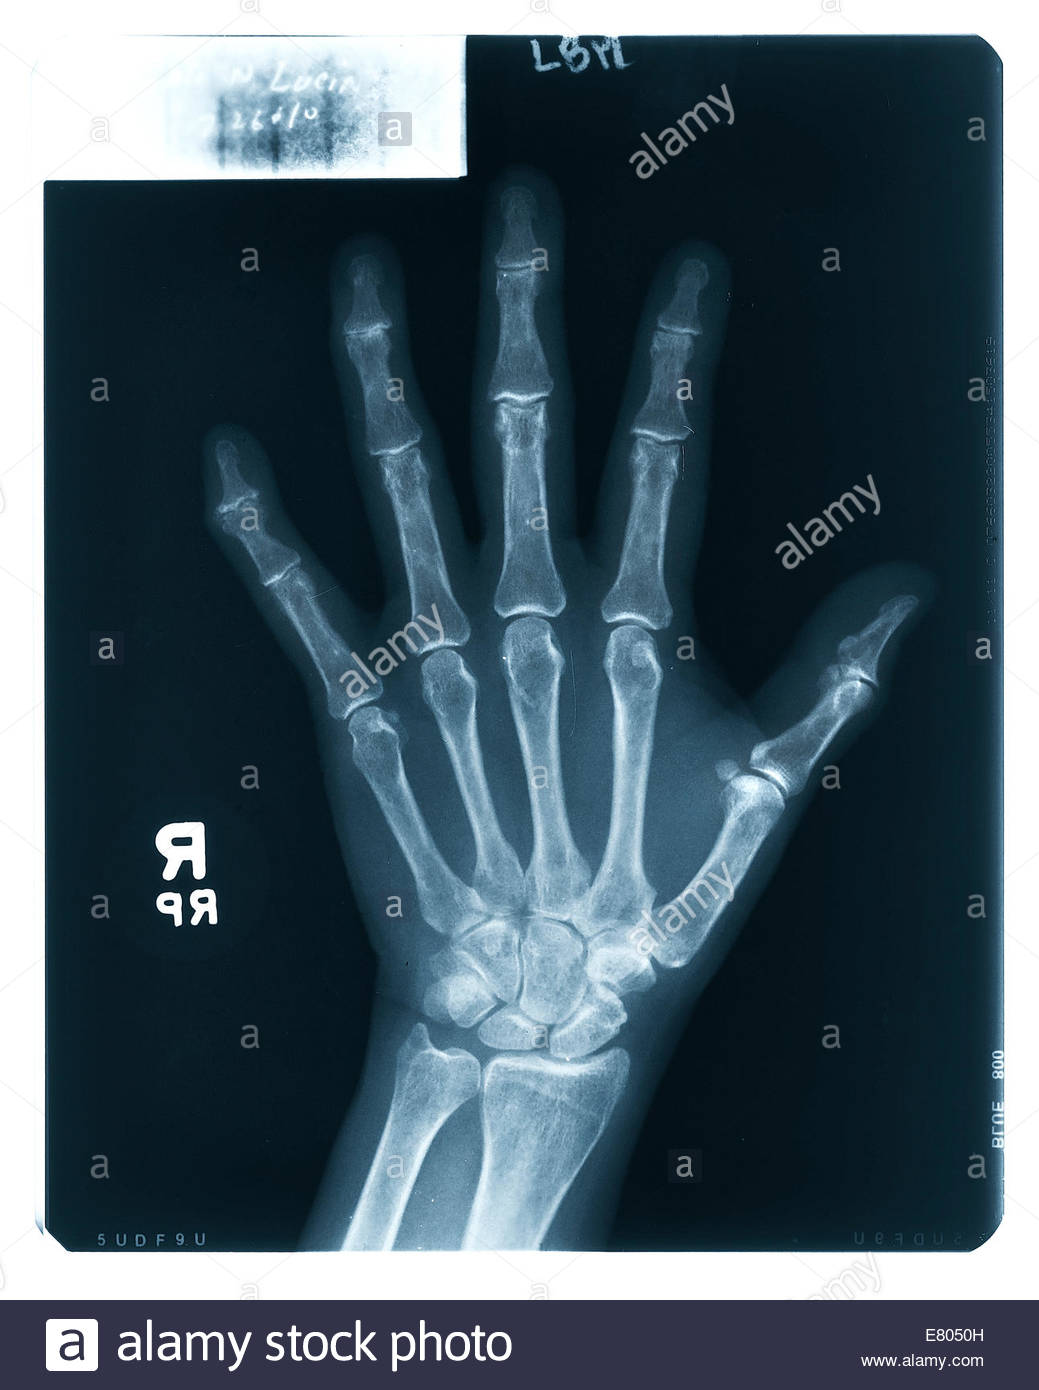

From www.alamy.com

hand xray showing a dislocation of the proximal interphalangeal joint Finger Joint X Ray Web the finger series is comprised, conventionally of a posteroanterior, oblique and a lateral view. Fractures and dislocations are usually straightforward to identify, so long as the potentially injured bone is fully visible in 2 planes. It is important to establish what forces were applied to the hand during the injury and the direction of these forces, as well as. Finger Joint X Ray.